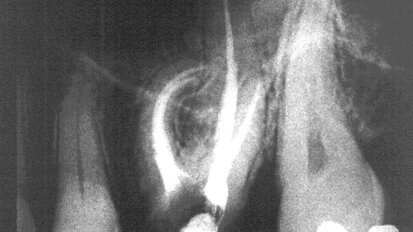

Lepljenje fragmenta i nadogradnja frakturiranog maksilarnog centralnog sekutića

Akutna dentalna trauma je veoma česta među decom mlađom od 12 godina. Najčešće povređivani zubi su maksilarni sekutići, a prilikom traume ...